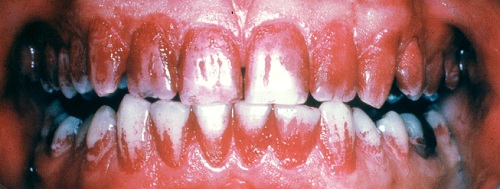

Farvestoffer til afsløring af plak på tænderne. Selv efter tre uger uden tandbørstning er der plakfri områder. Et område uden plak er et cariesfrit område. Med regelmæssig brug af tandbørste og tandtråd er det muligt helt at fjerne cariestruslen. Kun steder hvor plakken ikke fjernes regelmæssigt kan der opstå caries. I naturen er det den grove kost der fjerner plakken. Glatte tandoverflader er en evolutionær genistreg, der letter plakfjernelsen på de flader der udsættes for mindre slid. Formålet med regelmæssig plakfjernelse er at få fjernet plakken fra de tandoverflader, hvor almindelig tygning ikke fjerner plakken (plak-stagnations-områderne). (Else Theilade).